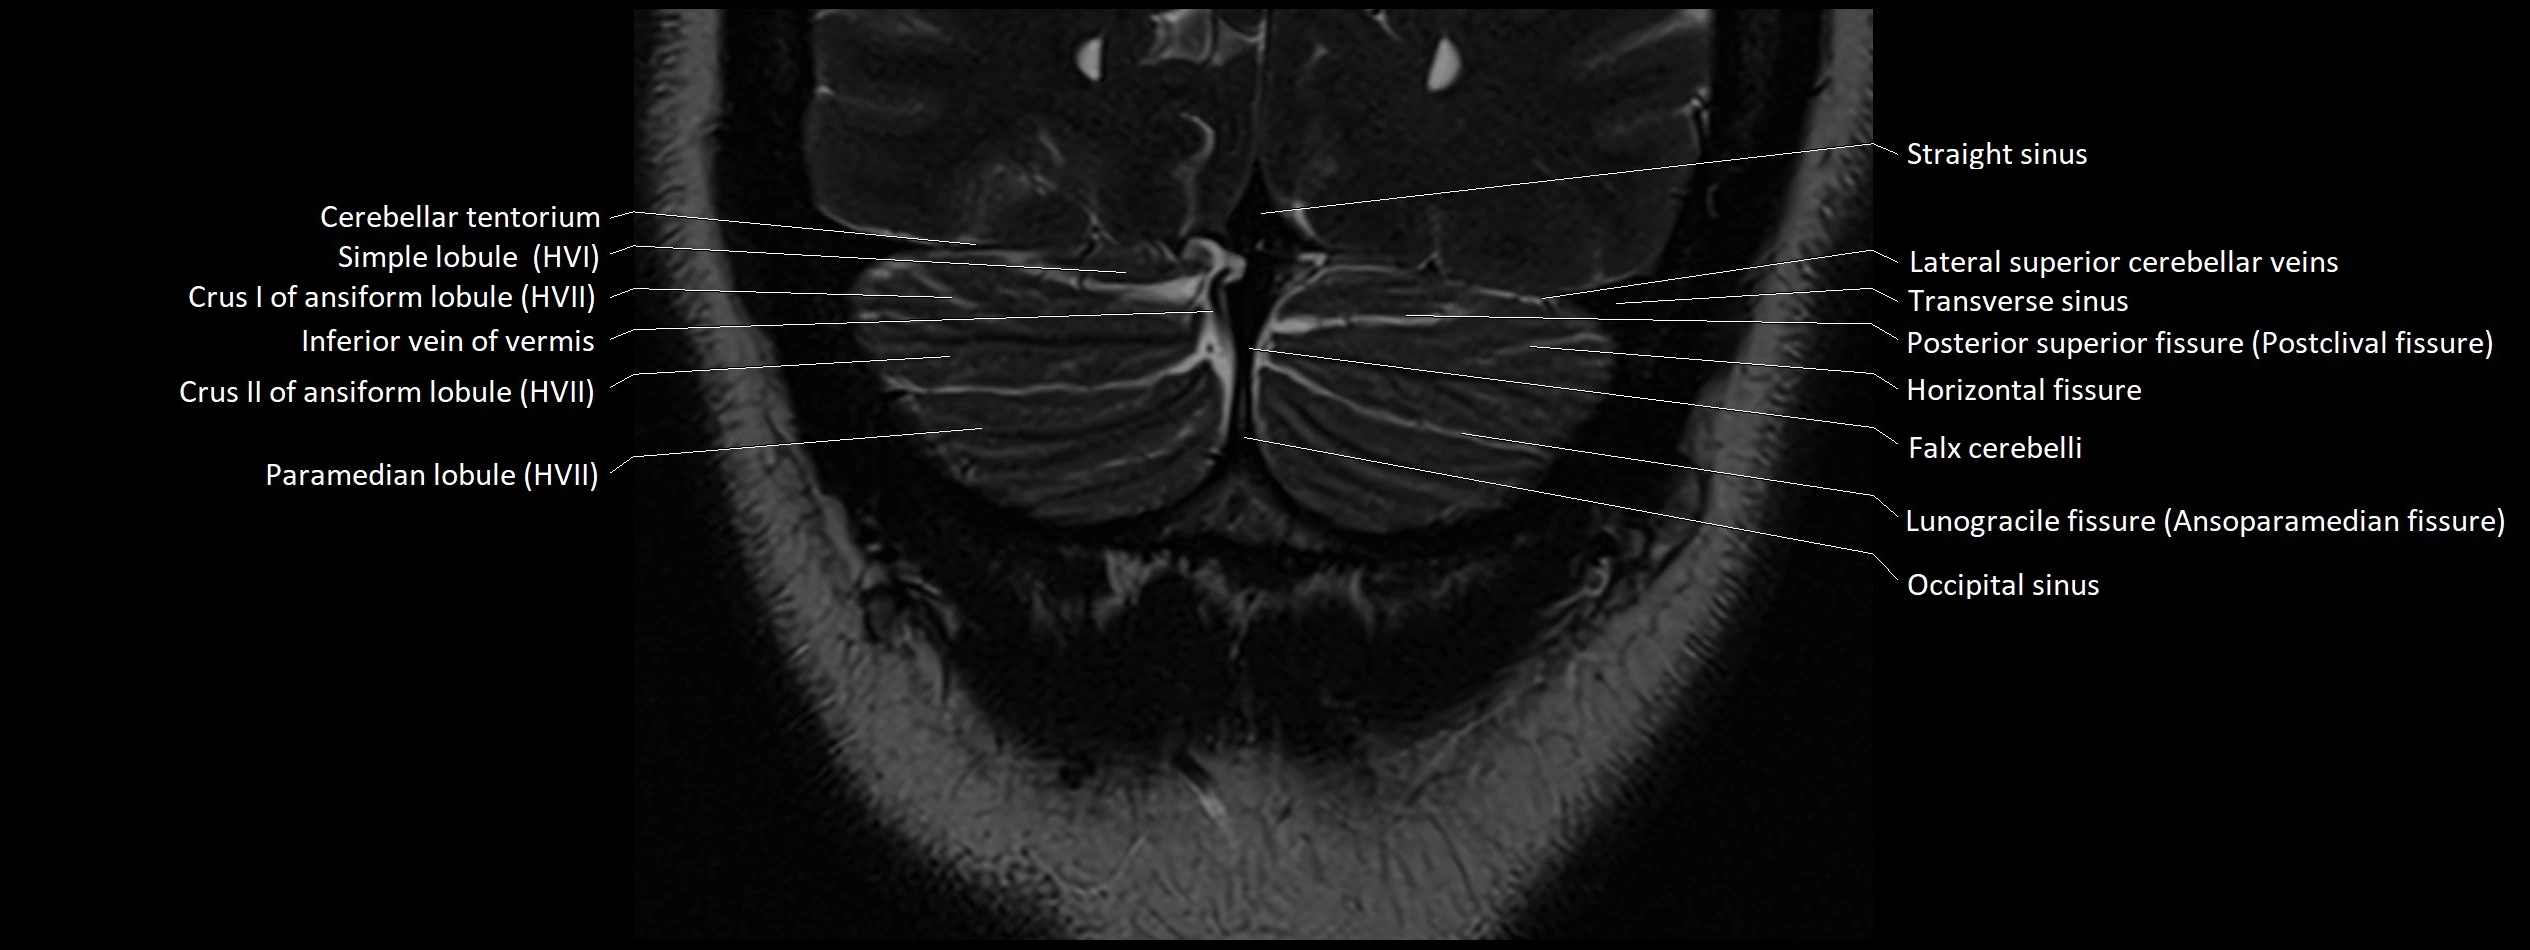

MRI images